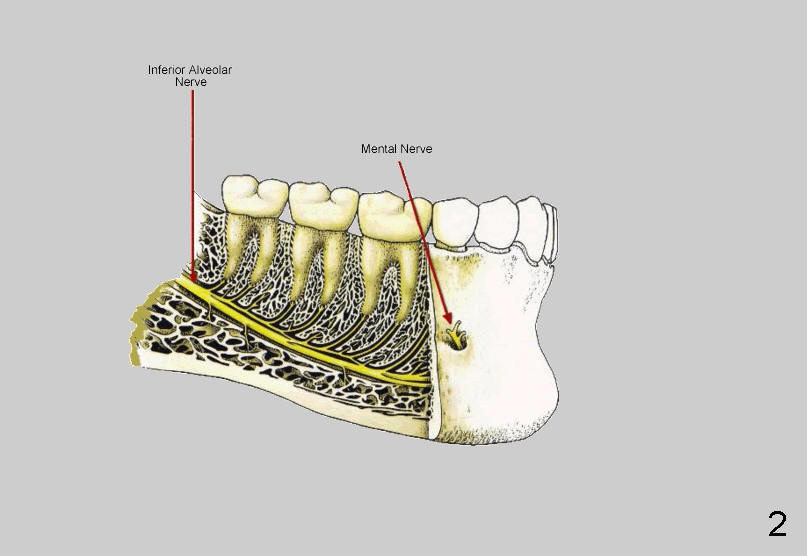

图一显示下颌骨侧面,绿色代表下颌孔,下齿槽神经由此进入,从颏(ke)孔出来(箭头)。颏孔位于第一,第二下前臼齿之间,如果我们拿探针插入颏孔,方向如箭头表示:往前往下,说明颏神经(图二:Mental nerve)却从相反方向出来,颏神经襻由图三Anterior loop of mental nerve表示。颏神经(襻)变异很大(图四红色),颏神经从下齿槽神经(黄色)分出后,后者继续往前行走,成为切牙神经(图四蓝色,图五Incisive nerve),支配下前牙。颏部取骨(Chin block harvesting)可能造成暂时性下前牙感觉减退,或者术中出血,压迫就可以止血。下切牙植牙钻洞可能损伤切牙血管,但是种植体植入后便止血。